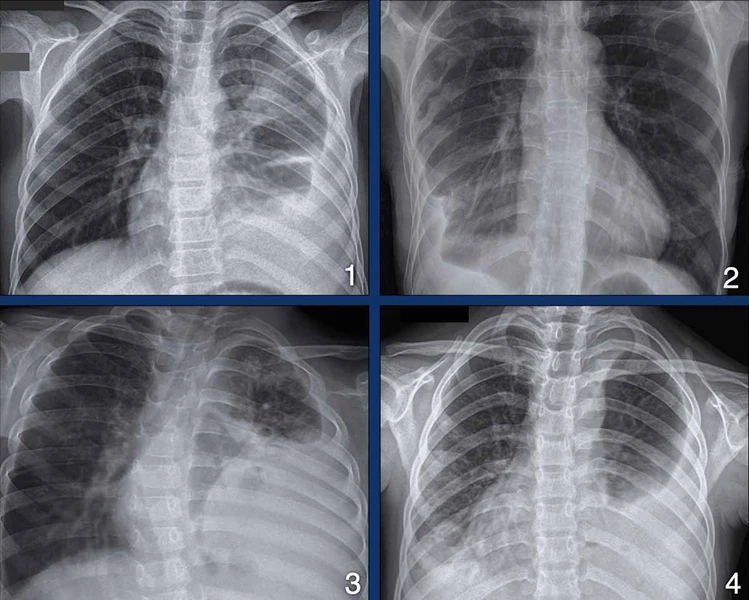

4. Цээжний X-ray-д илрэх өвчинийг Cases дээр тайлбарлах

MNT 30,000.00 or Chest X-Ray